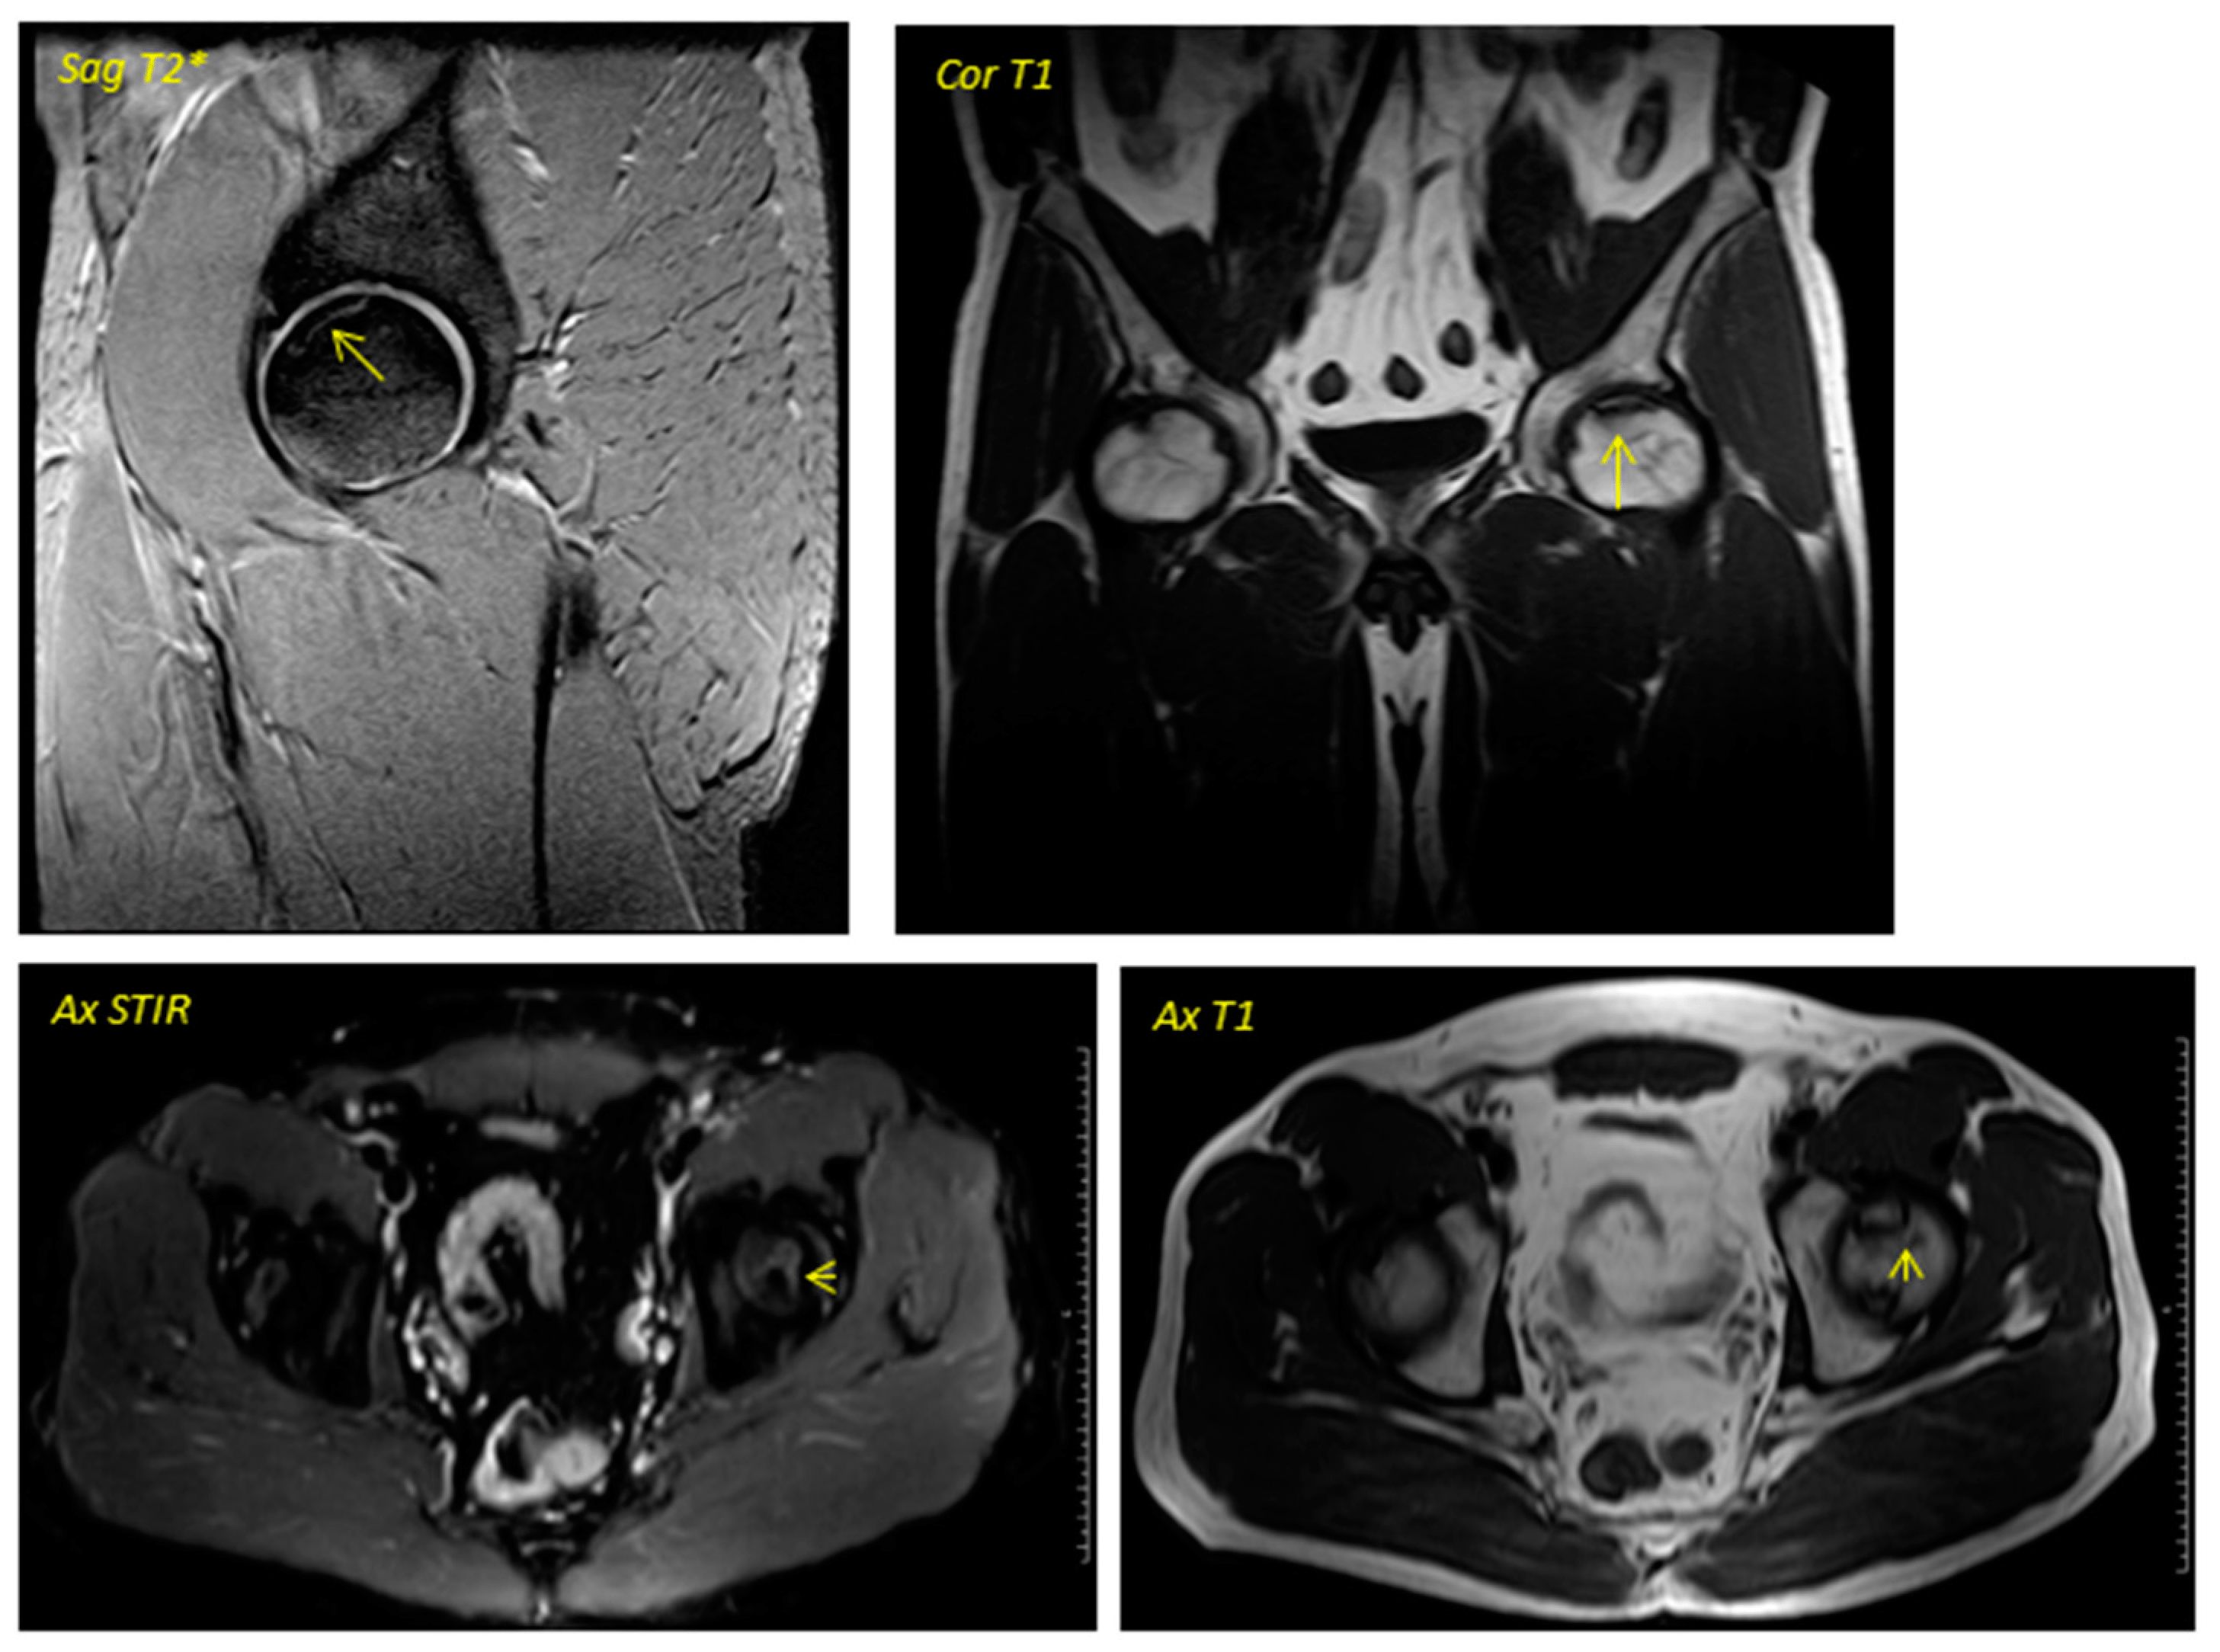

關(guān)于影像學(xué)研究,在12個(gè)月的隨訪(fǎng)期間,在影像學(xué)演變中觀(guān)察到了一些發(fā)現(xiàn)(圖1和圖2)。

首先,方向的變化從第六個(gè)月開(kāi)始出現(xiàn)在所有病例中,而在早期階段并不明顯。其次,62.5%的患者 ( n=5) 在手術(shù)后的第一年內(nèi)實(shí)現(xiàn)了影像穩(wěn)定。第三,兩名患者 (25%) 出現(xiàn)壞死區(qū)進(jìn)展,而一名 (12.5%) 患者出現(xiàn)明顯的再骨化跡象。盡管觀(guān)察到描述性差異,但后一個(gè)參數(shù)的p值在統(tǒng)計(jì)學(xué)上并不顯著。